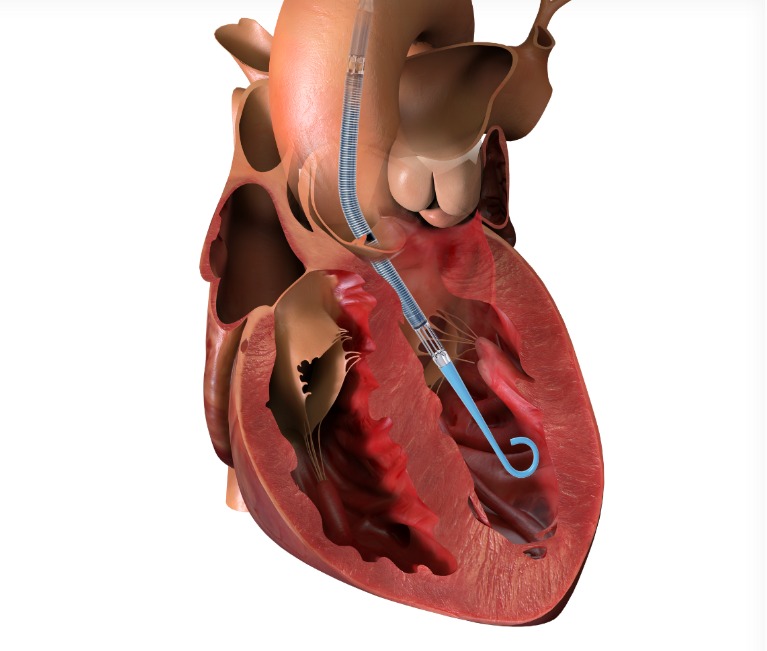

Enter the Impella – a tiny mechanical pump (thinner than a pencil!) inserted through the leg that travels to the heart. Think of it as a backup generator that keeps your house running while electricians fix the main power system.

With Impella supporting his heart, we performed BOTH procedures in ONE session: